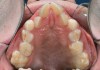

Fig 12. Palatal crib used to passively close bite and break thumb-sucking habit, at delivery (Fig 12), 6 weeks (Fig 13), and 12 weeks (Fig 14).

Figure 12

Fig 13. Palatal crib used to passively close bite and break thumb-sucking habit, at delivery (Fig 12), 6 weeks (Fig 13), and 12 weeks (Fig 14).

Figure 13

Fig 14. Palatal crib used to passively close bite and break thumb-sucking habit, at delivery (Fig 12), 6 weeks (Fig 13), and 12 weeks (Fig 14).

Figure 14

Tongue and thumb pressures also contribute to a high-vaulted palate, which can lead to mouth breathing (Figure 11).31 Additional risks exist for infection and callus development on the thumb. Ideally, the child should quit this habit by age 4, before permanent occlusal changes develop.32 Quitting can be achieved through positive reinforcement and by offering the child comfort during thumb-sucking triggers. The use of bitterants (eg, Mavala Stop, Thum, Control-It!), which are painted on or rubbed into the thumb, is another option.33 A habit breaker appliance may also be utilized if these techniques are unsuccessful. Devices such as a palatal crib, rake, or bluegrass appliance interfere with the thumb and tongue habits and allow the bite to passively close.34 The author recommends utilizing a habit breaker appliance for 6 to 9 months and maintaining reinforcement for a few months once the habit is eliminated (Figure 12 through Figure 14).